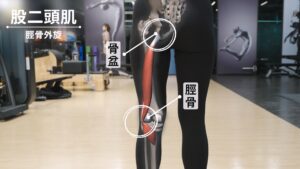

再來,股二頭肌

股二頭肌是一條從骨盆,連接到脛骨外側的肌肉,可以幫助脛骨做出外旋的動作。

當脛骨無法內旋時,大腿後外側的股二頭肌就容易變緊。

如果長期卡在外旋,這條肌肉就會因為長期缺少伸縮的動作而變得緊繃,讓膝蓋後側的肌腱壓力變大。

你看,膕肌還有股二頭肌,這兩條肌肉的肌腱,在膝蓋後側是不是重疊了。

因為這兩條肌腱重疊的地方,就是你會痛的地方,

這就是為什麼脛骨無法內旋的話,跑久了膝蓋後側痛的原因。